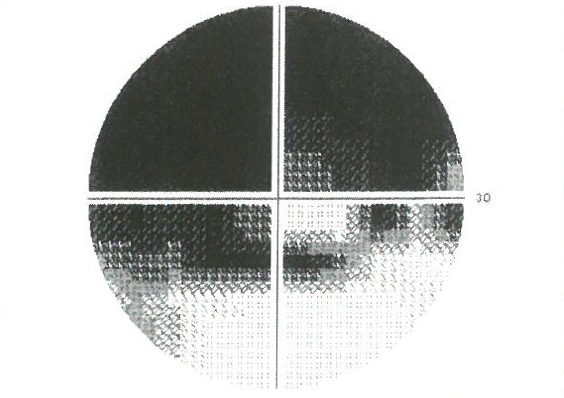

03.視野検査

緑内障の診断に視野検査はとても大切な検査です。緑内障の進行具合によって間隔は異なりますが、定期的に行う必要があります。当院では基本的にはハンフリー視野計で計測し、自動解析装置(ビーライン)で進行具合のチエックを行います。ハンフリー視野計で検査ができない場合や症状によっては、ゴールドマン視野計を用いて検査します。

緑内障の診断の原則は、眼底検査で視神経が減った場所があり、それに一致して視野の異常がみられる場合に緑内障と診断します。